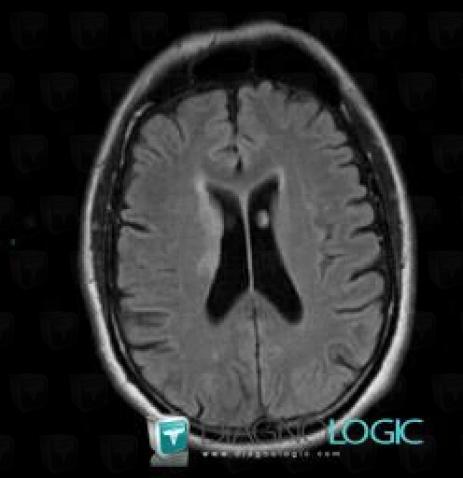

Cerebral infarction, Basal ganglia and capsule, MRI

Here is the specific information in the key image above:

- Diagnosis Cerebral infarction, Location(s) Basal ganglia and capsule, with gamuts DWI hyperintense lesion